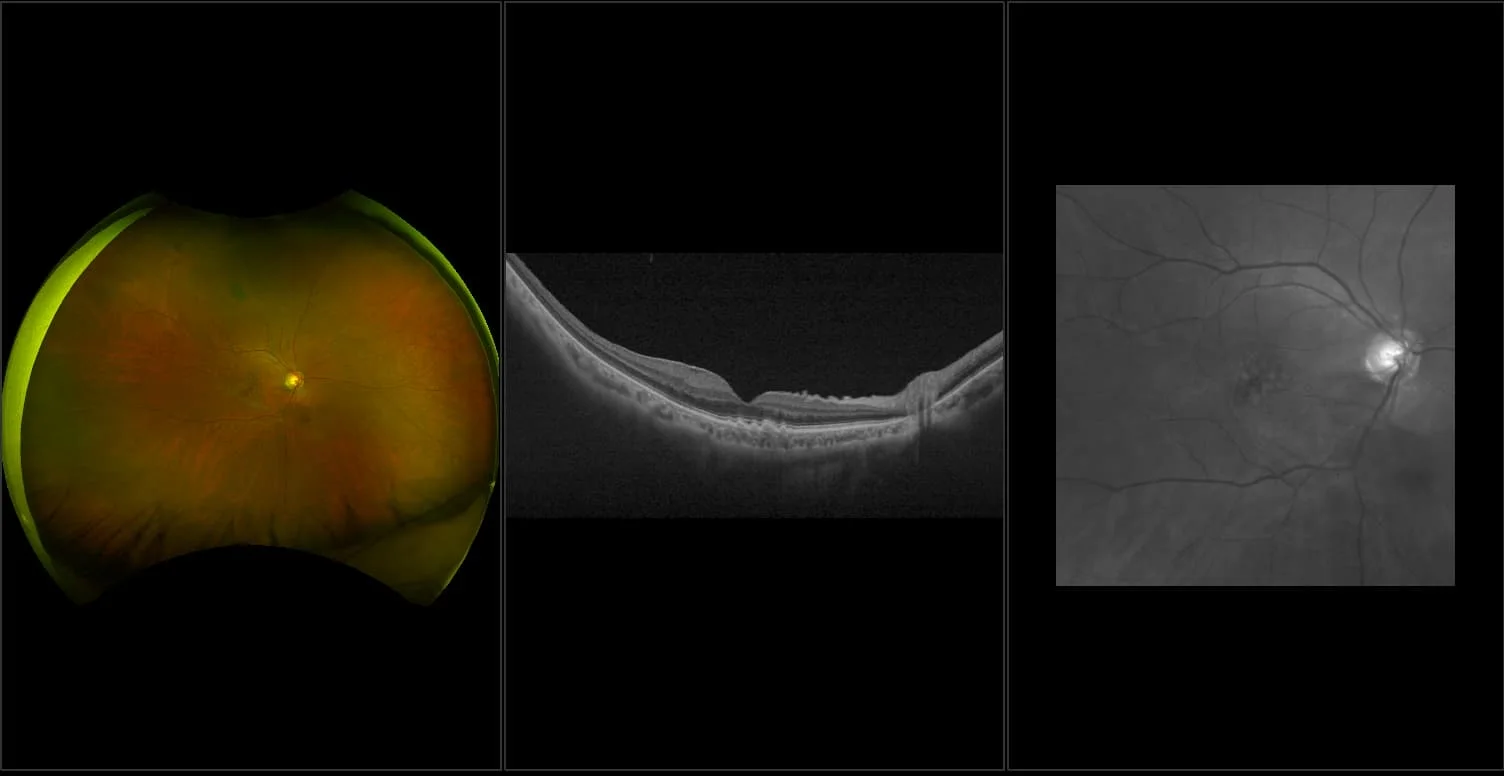

Silverstone - Dry AMD with ERM, RG, OCT

Age-related macular degeneration is found in two forms 1. Dry early form. 2. Wet (serous leakage or whole blood). Early dry form typically has drusen (usually around 63u) and RPE degeneration and only needs periodic follow-ups, intermediate dry form has large drusen (>125u) and RPE degeneration and proliferation which requires examinations every 3 to 6 months depending on the severity of the presentation.